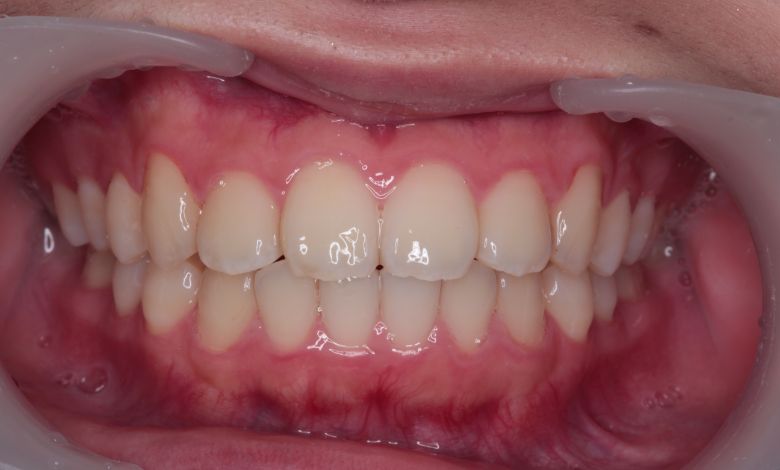

上下の歯がしっかりと噛み合う、美しい咬合(こうごう)が得られた

精密検査の結果、当院では抜歯を行わず、歯列弓の拡大によってスペースを確保し、非抜歯での矯正治療を選択しました。歯列の叢生(ガタガタ)は解消され、機能的かつ審美的に優れた咬合が得られました。

上下の前歯の重なりが解消され、歯軸の傾きも整いました。咬合関係も安定しています

術前に認められた前歯3本の強い重なりは完全に解消され、スムーズな歯列が形成されました。